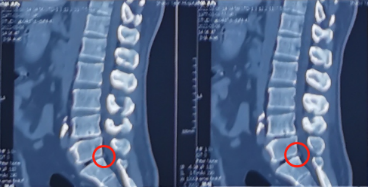

“医生,我腰疼”丨腰椎间盘突出症怎么治?

医生,我腰疼! 45岁的马先生因 腰部疼痛伴右下肢放射痛1年多 来到陕西冶金医院神经脊柱科就诊 近1年来马先生腰部疼痛伴右下肢放射痛 腿脚发麻,久站受凉后症状加重 一直没有引起

没有假期的中年人遇上腰腿痛,如何是好?一个小孔快速解决腰椎间盘突出问题!

痛!赶不走的腰腿疼! 痛!痛!痛! 对于44岁的吕先生(化名)来说 最近一段时间的生活充斥着这个字 自从1年前,他没有明显诱因地 出现了腰痛及右腿放射性疼痛之后 就经常被这样的病痛困扰

不要让腰椎间盘突出成为你全身最突出的亮点丨陕西冶金医院骨科有办法!

腰椎间盘突出症 一个常见病,多发病 发病率还在逐年上升 是腰背痛最主要的发病机制 80%的患者在20岁-50岁 70岁以上也可遇到 职业分布可见于各行各业 主要是长期弯腰干活或长期坐位